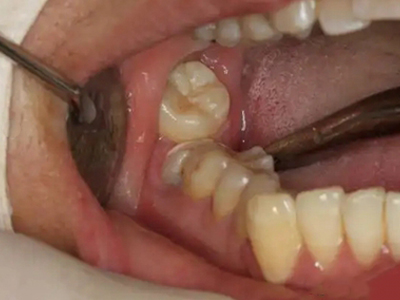

阻生牙是指由于邻牙、骨或软组织的阻碍而只能部分萌出或完全不能萌出,且以后也不能萌出的牙。引起牙阻生的成因,主要是由于颌骨缺乏足够的空间容纳全部恒牙。常见的阻生牙为下颌第三磨牙、上颌第三磨牙及上颌尖牙。

阻生牙可反复引起冠周炎,或引起邻牙牙根吸收和破坏,位置不正,不能完全萌出,好发部位是上、下颌第三磨牙。

对于阻生牙的处置需要首先明确阻生牙齿发育情况是否正常,对于由于早期外伤或其他原因造成发育异常,如牙根弯曲、短根等情况的阻生牙,还应根据患者的综合情况,决定牙齿是否保留。